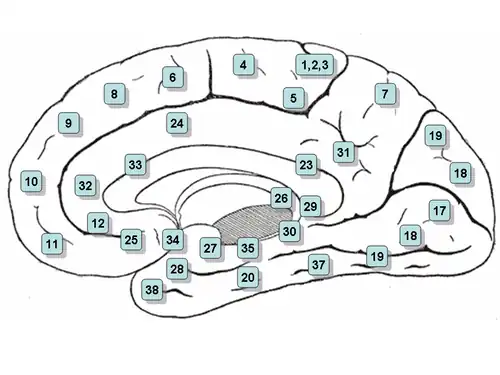

Medial surface of the brain with Brodmann's areas numbered. | |

Brodmann area 33, also known as pregenual area 33, is a subdivision of the cytoarchitecturally defined cingulate region of cerebral cortex. It is a narrow band located in the anterior cingulate gyrus adjacent to the supracallosal gyrus in the depth of the callosal sulcus, near the genu of the corpus callosum.[1] Cytoarchitecturally it is bounded by the ventral anterior cingulate area 24 and the supracallosal gyrus (Brodmann-1909). The pregenual area 33 is heavily involved in emotions, especially happy emotions.[2][3]